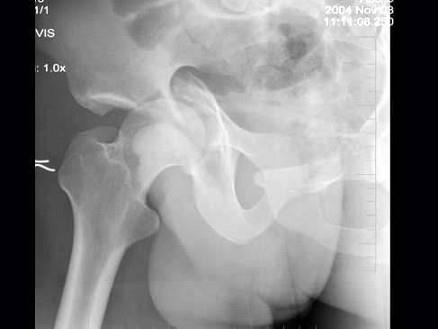

问题 男,32岁,因车祸致右髋关节肿痛,活动受限摄片如图示,最可能的诊断是?(?)

选项 A.骨盆Ⅰ型骨折 B.骨盆Ⅱ型骨折 C.骨盆Ⅲ型骨折 D.骨盆Ⅳ型骨折 E.以上均不是

答案 D